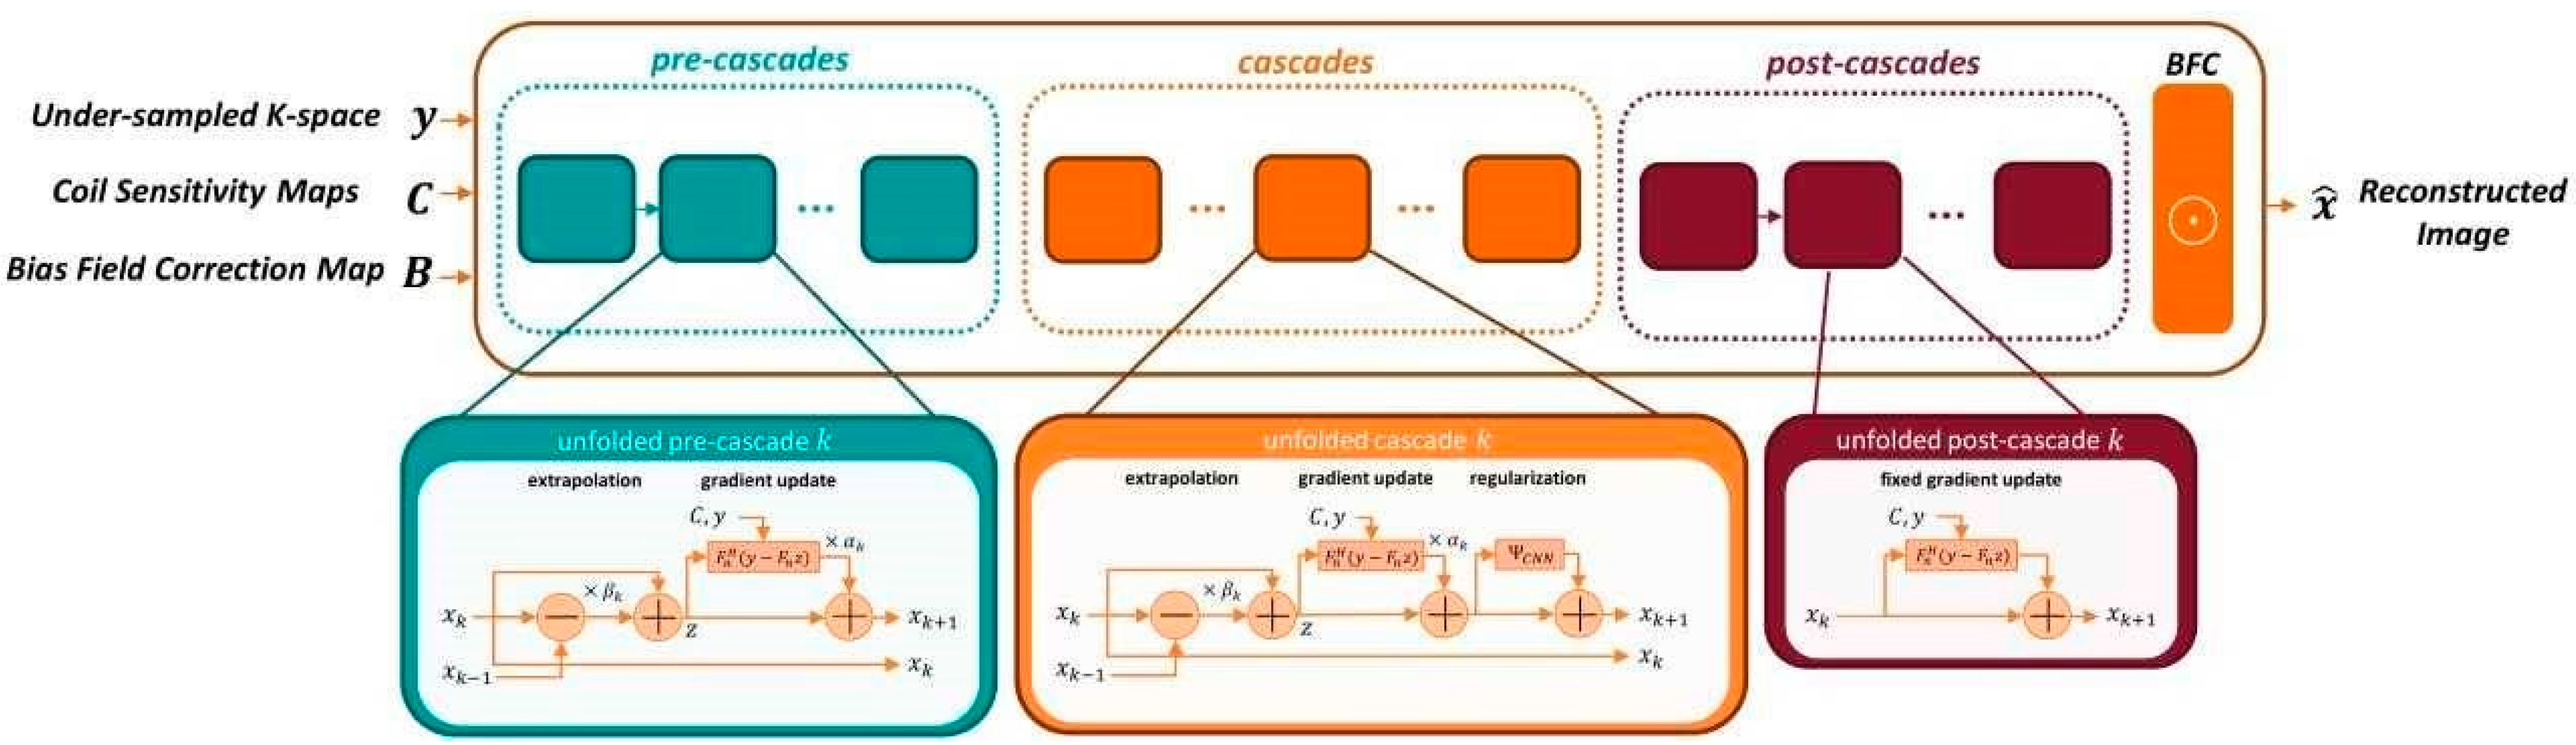

2.2. Deep Learning Image Reconstruction

2.3. Implementation of DL Image Reconstruction in Clinical Workflow